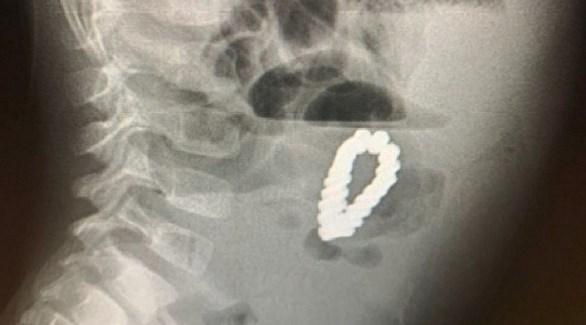

وقالت مجلة Paediatric Surgery Case Reports الأمريكية إن الأطباء أصيبوا بالحيرة، عندما كشفت عمليات المسح أن الطفل البالغ من العمر 4 سنوات كان يحمل بداخله سواراً مغناطيسياً.

ورغم إزالة الزائدة الدودية استمرت آلام الطفل، وعندما أجرى الأطباء عمليات المسح، كانوا مندهشين لرؤية شيء على شكل سوار داخل بطن الطفل، وكان والداه مرتبكين بنفس القدر.

وبشكل لا يصدق، يعتقد الأطباء أن الصبي قد ابتلع كل حبة مغناطيسية على حدة خلال مدة غير معروفة، ولكن بسبب خصائصها المغناطيسية، فقد تمكنت من الالتصاق ببعضها البعض مشكلة حلقة، ووصلت إلى حد سد أمعاء الصبي وحتى حفر ثقوب في أمعائه.

وأجرى الجراحون على الفور عملية فتح البطن على الطفل لإزالة 18 قطعة مغناطيسية سداسية الشكل، ثم سارعوا لإصلاح الضرر الذي لحق بأمعائه.